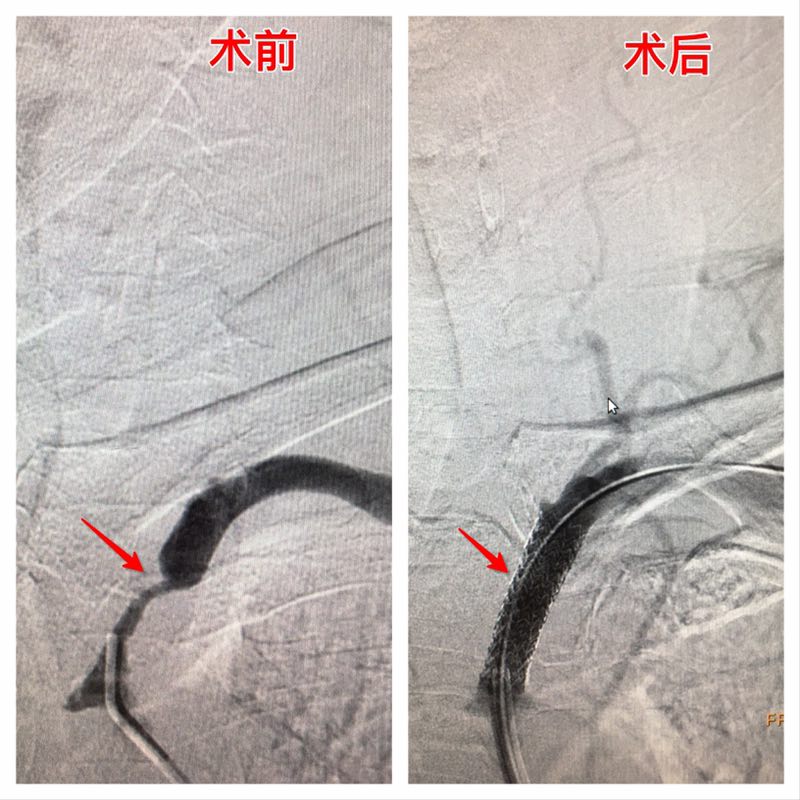

我院完成首例锁骨下动脉支架植入手术

患者周某,女性,80岁,因经常性头晕伴左上肢无力、肢体发凉收住入院。入院后测血压发现双上肢相差较大,右侧收缩压高达160mmHg,左侧收缩压仅为120mmHg,而且左侧桡动脉搏动较右侧明显减弱、皮肤苍白且皮温低,这些症状老太太一直瞒着家里人,经过我院DSA检查明确诊断为:1、左侧锁骨下动脉近端重度狭窄;2、锁骨下盗血综合征。高博士及我院神经介入团队经过精心准备,决定于5月20日在局麻下行“左侧锁骨下动脉支架植入术”,术中先于狭窄处用Armada5-40mm球囊在8个大气压下预扩张,造影显示扩张满意后再用Abbott Omnilink8-29mm支架在8个大气压下成功置入,手术过程非常顺利,虽然患者年龄较大,但由于微创手术创伤小、恢复快、并发症少,患者于术后3天痊愈出院。